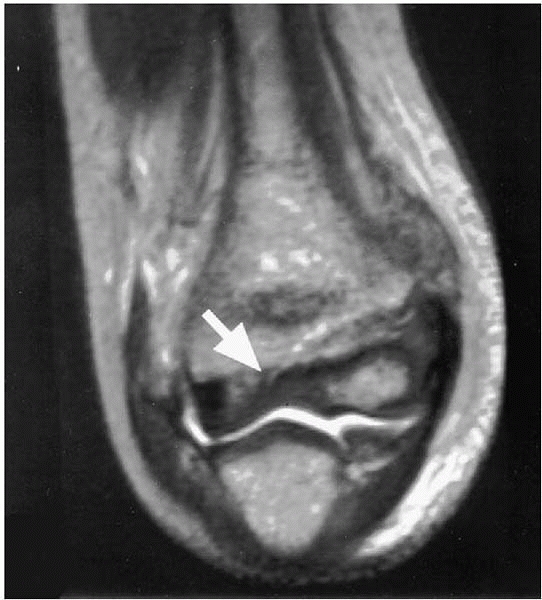

In questionable cases Dr. Beaty recommends using a gradient echo MRI in evaluating articular fractures of the elbow (Fig. 6-6).

▪ FIGURE 6-6

MRI of an elbow demonstrating a lateral condyle fracture in which the fracture line does not extend through the cartilage into the joint. Dr. Beaty reports that as time goes on some institutions will be utilizing MRI over arthrography in a number of cases. (Reprinted with permission from Horn BD, Herman MJ, Crisci K, et al. Fractures of the lateral humeral condyle: role of the cartilage hinge in fracture stability. J Pediatr Orthop. 2002;22(1):8-11.) |